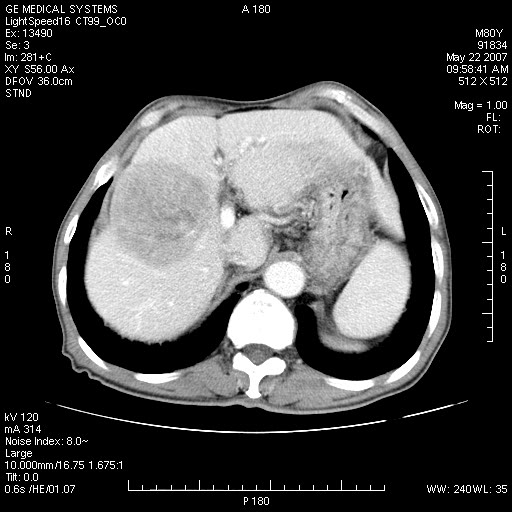

标题: CT8346:男,80岁。血尿,肝脏,膀胱占位,是否为肝转移?

男,80岁。血尿,无腹部不适病史。

肝脏病变:

肝脏内病灶有假包膜,增强扫描动脉期有动静脉瘘,有快进快出特点,考虑原发性肝癌。病灶内有裂隙样低密度影,以纤维板层样细胞癌可能性大。膀胱左侧乳头状占位,增强呈明显强化,左侧盆腔内有肿大淋巴结,结合有血尿病史,考虑膀胱癌左侧盆腔淋巴结转移。